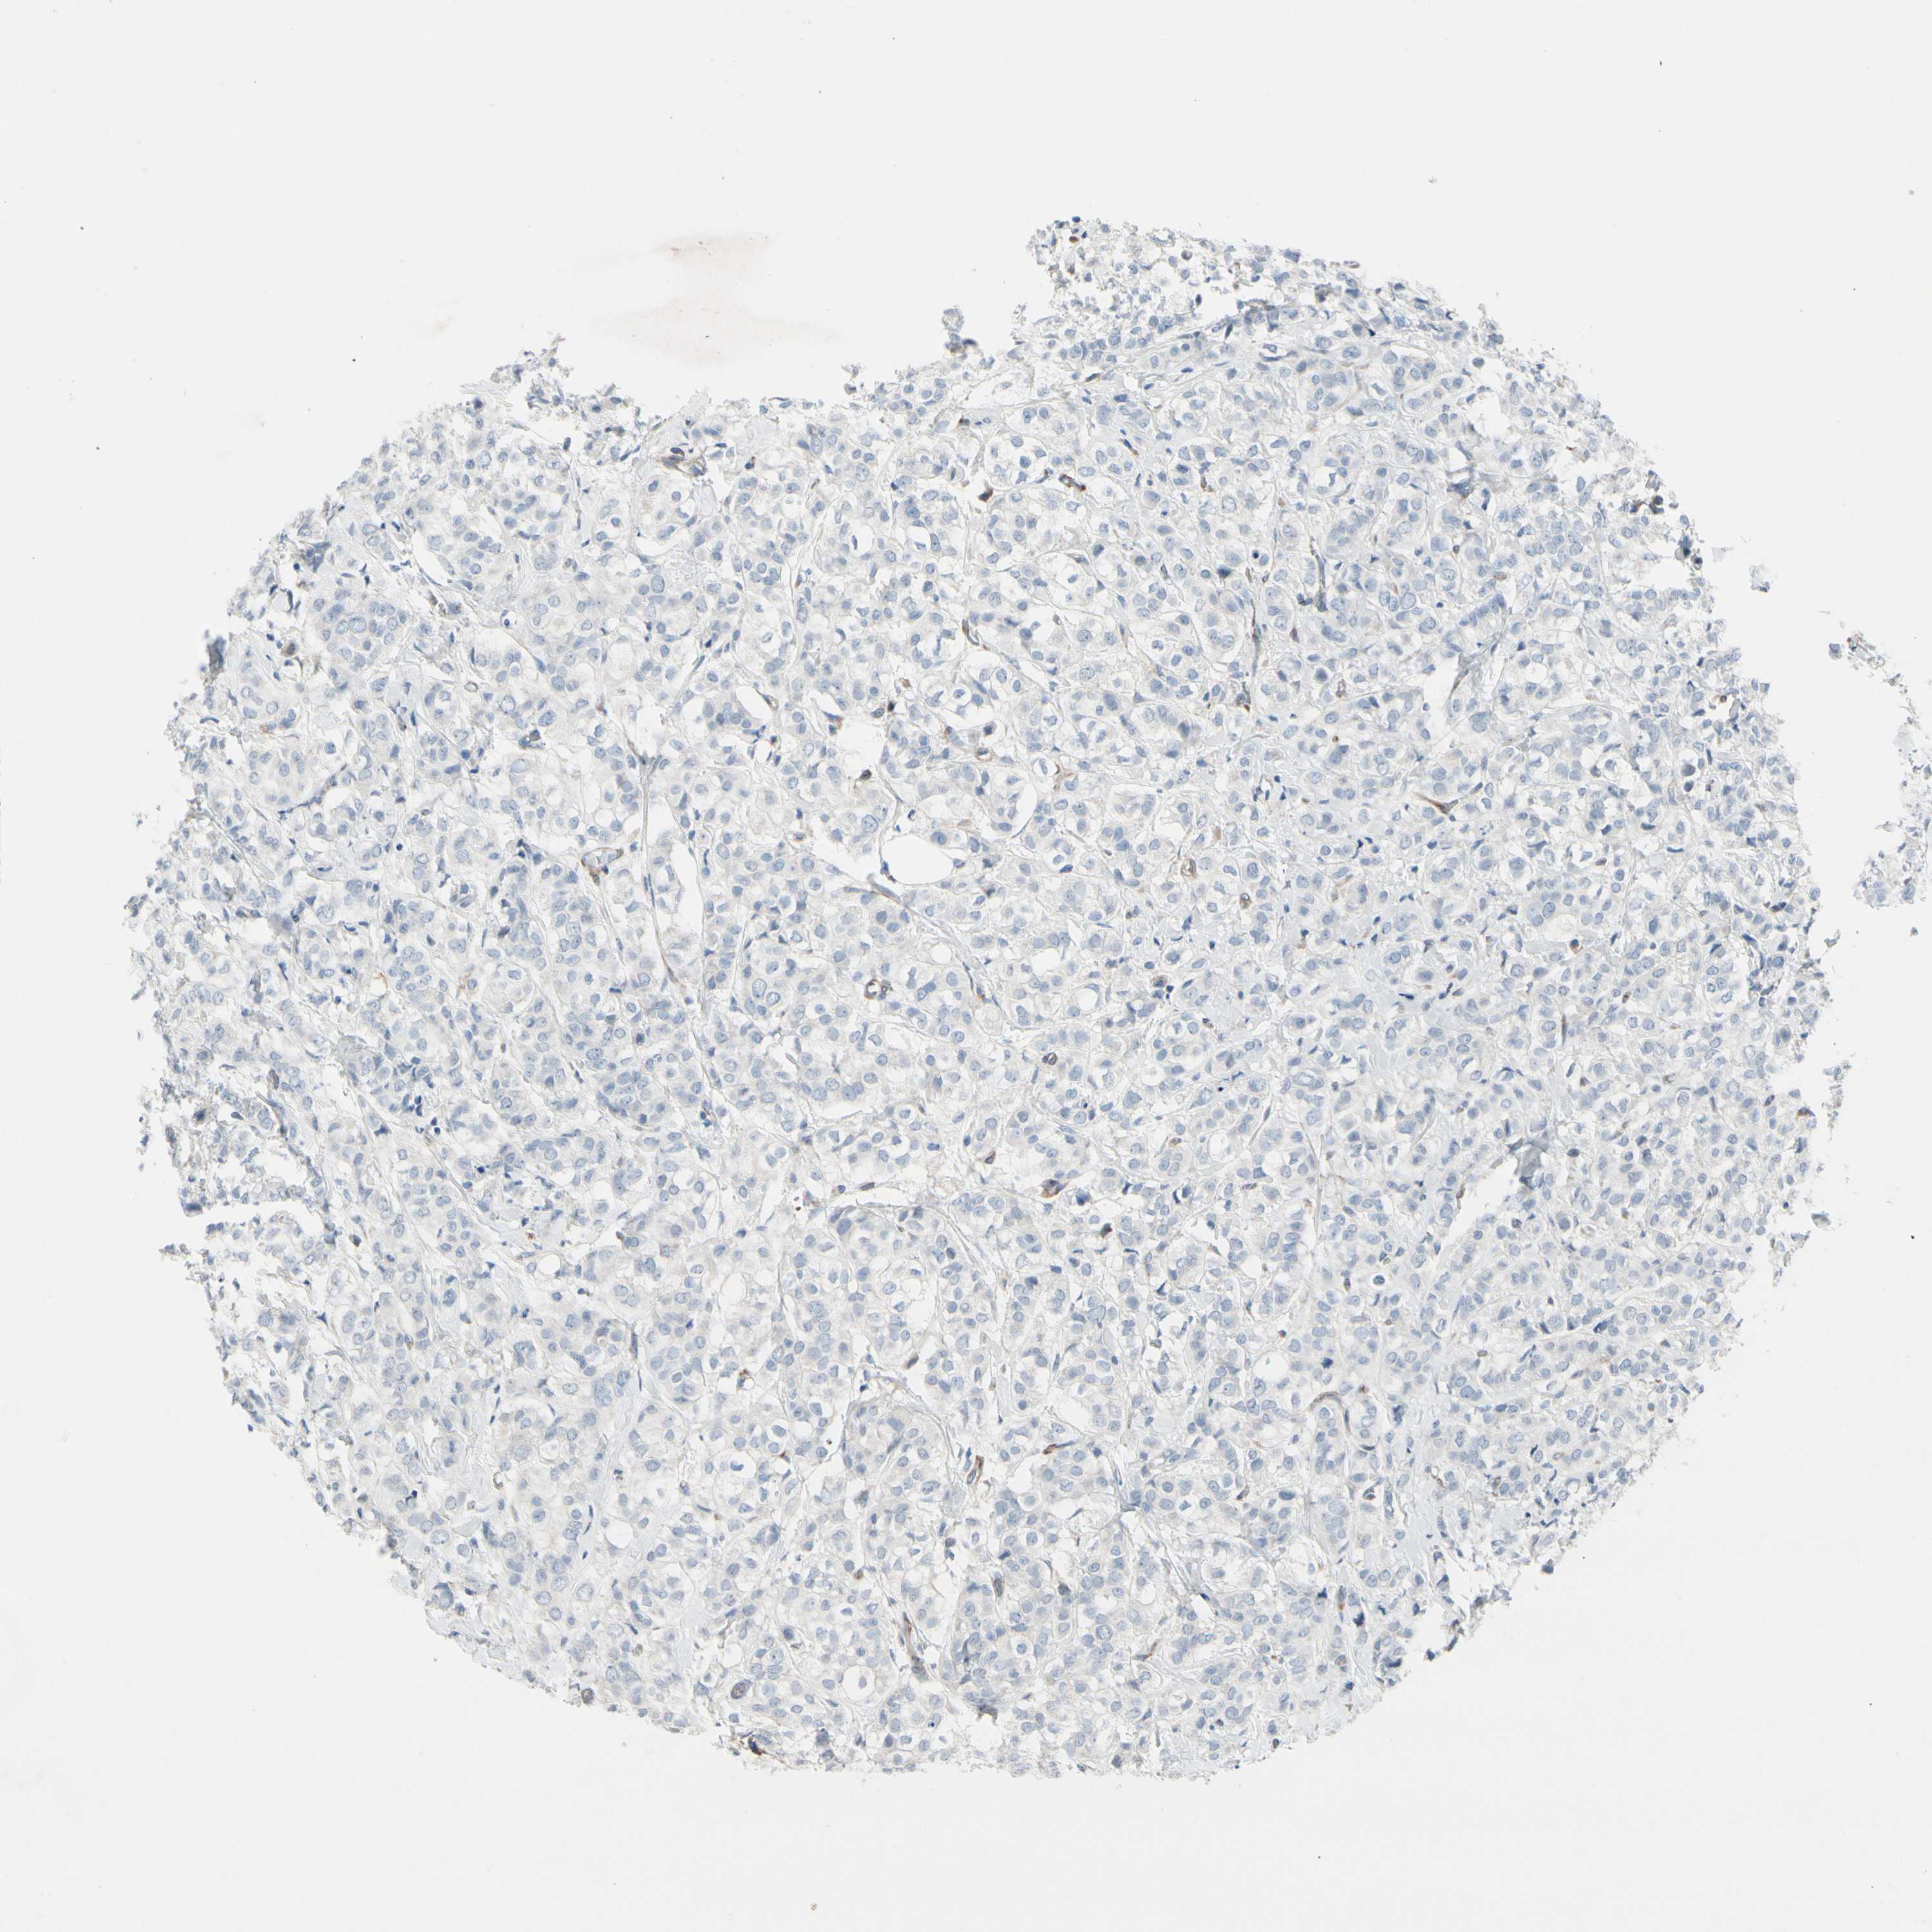

CANCER BREAST CANCER Show tissue menu

BRCA TCGA BRCA VALIDATION PROTEIN EXPRESSION

Breast cancer

Human cancer